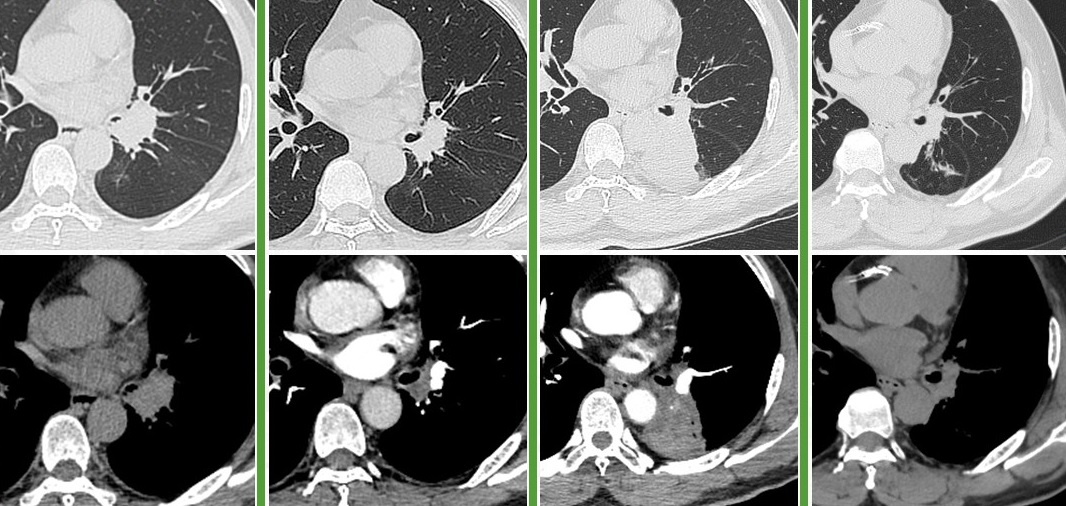

58岁,男,吸烟史40年×30支,2020.6出现咳嗽,CT见左肺门占位,气管镜取病理示小细胞癌,cT1cN0M0 IA3期,于当地医院行EP方案化疗4周期,病灶缩小,序贯胸部放疗。2021.4复查见左肺新发占位,又行TP方案化疗2周期,评效PD。2021.9来我中心就诊,气管镜再活检示小细胞癌,rT1cN1M0 IIB期局限期。予EP方案化疗2周期,评效SD,改安罗替尼+EP方案化疗4周期,评效SD-,后安罗替尼维持治疗。2023.9复查CT见左肺病变增大、左下肺部分不张,气管镜见左下肺开口狭窄,活检见肿瘤细胞,未行免疫组化。全身检查未见远处转移,行斯鲁利单抗+白蛋白紫杉醇化疗4周期,评效PR,后斯鲁利单抗维持治疗至今(17周期)。截至2025.2.20

治疗小结:1.EP×4序贯胸部放疗,PFS 10个月;

2.TP×2,PFS 1.5个月;

3.EP×2、安罗替尼+EP×4、安罗替尼,PFS 24个月;

4.斯鲁利单抗+白蛋白紫杉醇×4、斯鲁利单抗×17+,PFS 17个月+。

图:左起依次为三线治疗前、三线治疗后、四线治疗前、末次随访